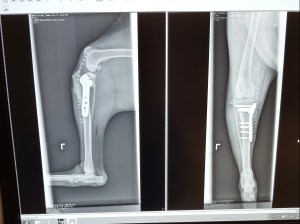

With TPLO surgery, the surgeon places a plate and screws into the bone after they have cut a curve in the tibia bone to reshaped it to allow for good movement and better stability. The CCL is removed because it can not be repaired and in some cases (like Brutus) the meniscus is found to be damaged and is also removed.

Here are pictures of Brutus’ knee showing before and after surgery. Pictures are taken just before surgery and then after the plate is in place, to compare and ensure proper placement before finishing up. The plate will be there for the rest of his life.